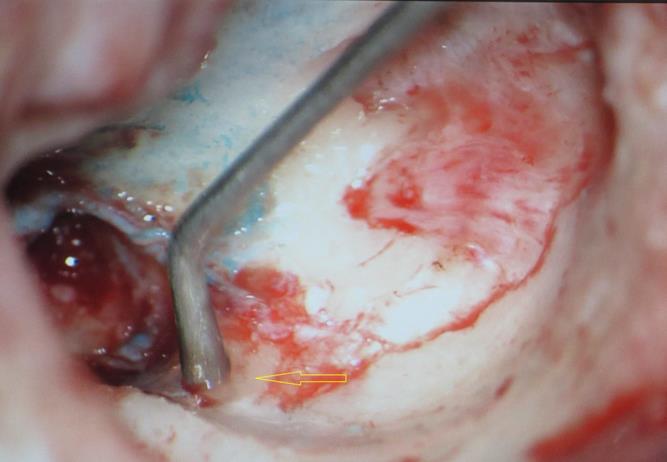

A 13 year old girl presented in ENT outpatient department with complains of recurrent right ear purulent discharge from pre and post auricular area for last 5 years. She had a history of incision and drainage in right post auricular area six months prior for similar complain. On local examination, there was right Grade II8microtia with atretic External Auditory Canal (EAC) and pre-auricular skin tag (Figure 1). A small fistulous opening was also seen in right cavum conchae region. Left ear examination was normal with intact tympanic membrane. Tuning fork tests using 256 and 512 Hz tuning forks showed moderate to severe conductive hearing loss in right ear with Rinne’s test positive in left ear. HRCT scan of temporal bones showed membranous atresia of right EAC with grade II microtia. Soft tissue density was seen filling the EAC and the entire middle ear cavity (Figure 2A). A CT based fistulogram done four months before our consultation identified multiple fistulous tracts situated in post auricular region and anterior to stylomastoid foramen in inframastoid region. These fistulous tracts were communicating through middle ear cavity (Figure 2B). There was associated erosion of posteroinferior and anteroinferior wall of EAC. Ossicles were dysplastic or eroded. Inner ear structures were normal. Patient underwent right radical mastoidectomy with wide conchal meatoplasty under general anaesthesia. Intraoperatively, there was right EAC membranous atresia with fistulous opening in cavum conchae. Cholesteatoma sac was seen filling the mastoid antrum area extending into middle ear cavity and EAC with erosion of posterior canal wall. Except remnant of malleus head which was fixed to epitympanic wall, no other ossicle was found. Oval window area showed bony depression without any overlying stapes footplate (Figure 3). Lateral semicircular canal bulge, facial nerve canal and chorda tympani were found at their usual locations (Figure 4). Obliteration of mastoid cavity posterior to vertical segment of bony facial canal was done using pedicled temporalis muscle flap to reduce the size of postoperative cavity. Middle ear cavity was covered with temporalis fascia graft.

Figure 3.Arrow pointing towards oval window area